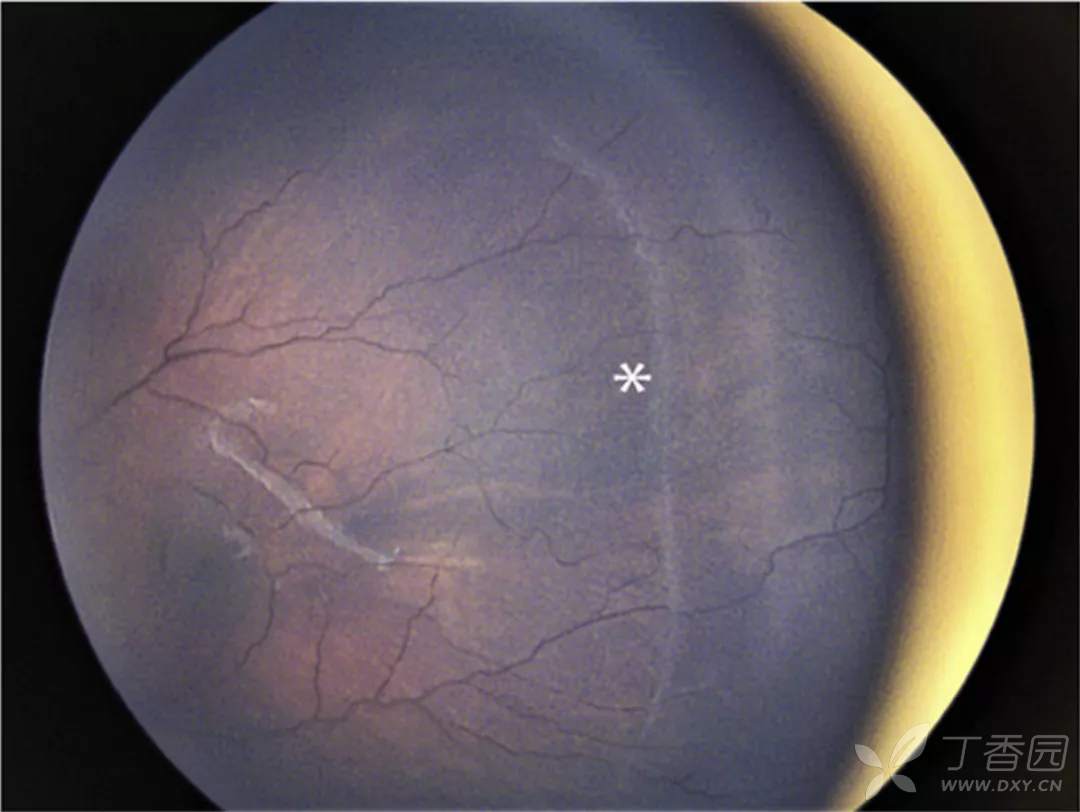

图. 15岁患儿有极度早产史,之前无ROP治疗史,超广角眼底图像(左侧)可见不完全消退的与持续性视网膜无血管区(星号)。2年后(右侧)患者出现累及黄斑部的孔源性